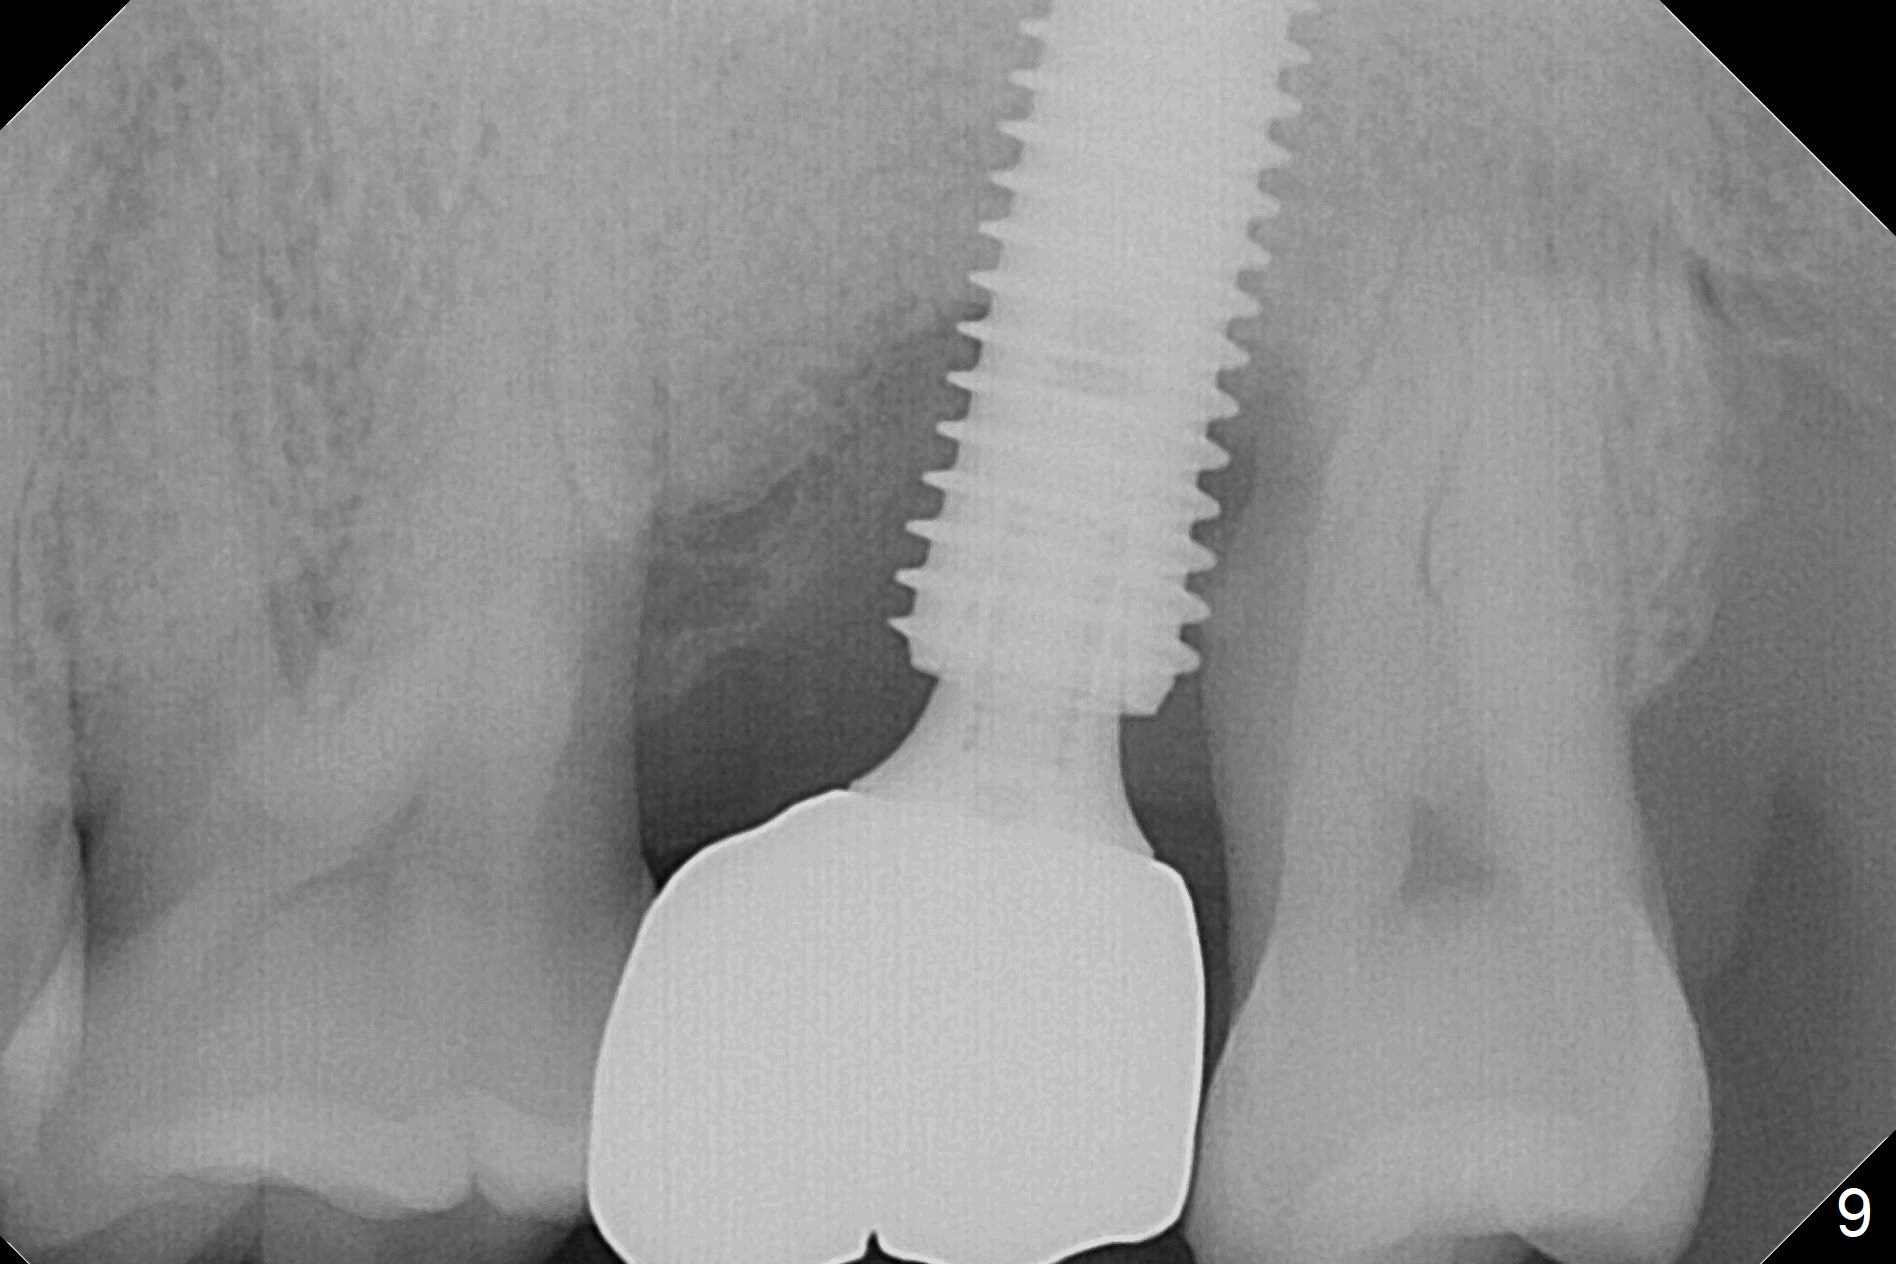

There is severe gingival recession: 15 DB, implant plateau exposure, surrounded by healthy granulation tissue, 3.5 months postop. PA shows #15 + implant osteointegration and bone loss coronally (Fig.7). Afterward, the abutment is changed from 6.5x4(4) to 5.5x5(2) mm with fabrication of a provisional. The patient feels that it is easier to brush with a temporary crown. Model shows gingival recession (Fig.8 G) with implant thread exposure distobuccally (I). Although there is no obvious change in bone regeneration 7.5 months postop (2.5 months post cementation, Fig.9) as compared to Fig.7, there is no more distobuccal gingival recession (data not shown; due to use of Water Pik). To avoid the gingival recession, the implant should have been placed more mesial and deeper (Fig.10 green) with use of a longer-cuff (pink) abutment.